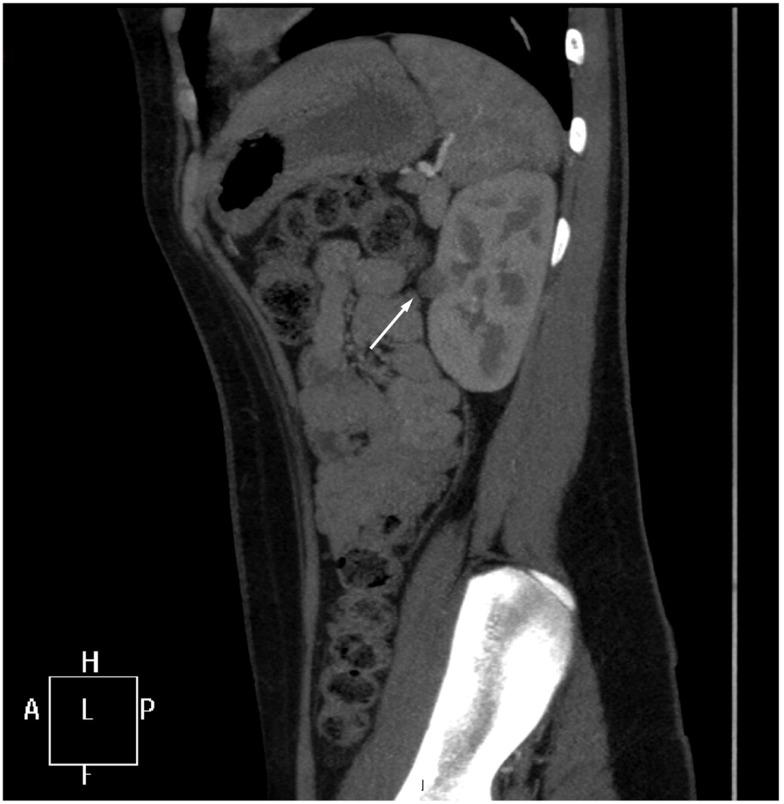

Reninoma (juxtaglomerular cell tumor) is a rare cause of renin-mediated hypertension. Reninomas are usually diagnosed in adolescents and young adults with occasional reports in younger children. Patients typically present with a long history of headaches leading to a diagnosis of severe hypertension that responds well to antihypertensive treatment targeting the renin-angiotensin-aldosterone system. The clue to clinical diagnosis is the presence of hypokalemia and metabolic alkalosis on the first blood sample drawn before any treatment is instituted. Elevated blood levels of renin and aldosterone confirm the clinical suspicion of renin-mediated hypertension. Diagnostic imaging is employed to identify the source of excessive renin production. While renal ultrasound can miss reninoma, contrast CT or magnetic resonance imaging of the kidneys are diagnostic modalities of choice leading to the correct diagnosis. Renal vein renin sampling with lateralization might help to identify the site of excessive renin production. Nephron-sparing surgery is curative with maintenance of normal blood pressure after discontinuation of antihypertensive medications in the majority of patients. In this paper, we present the case of reninoma in an adolescent girl emphasizing clinical presentation, diagnostic evaluation, and medical and surgical treatment of this rare tumor. We also discuss important points in the management of children presenting with renin-mediated hypertension.